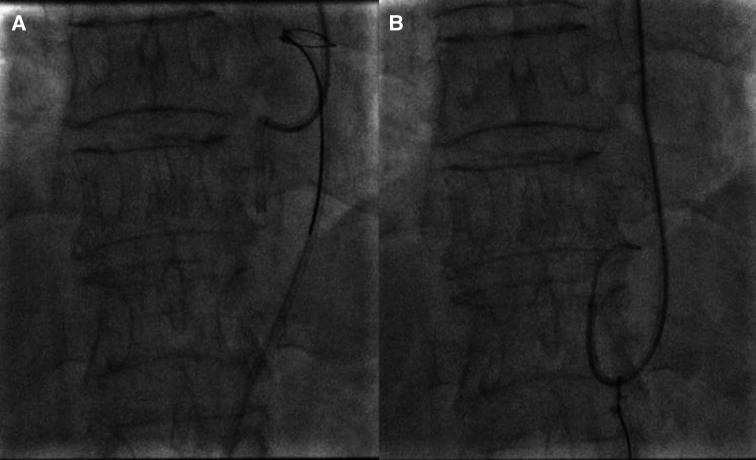

A male patient in his 60s, an ex-smoker, had recent anterior myocardial infarction and coronary angiography was done after thrombolysis in another centre that showed tight proximal left anterior descending (LAD) artery lesion (figure 1A).

Figure 1.

Tight left anterior descending lesion (A) before stenting and (B) after stenting.

A patient in his 60s was referred to our centre for revascularisation and percutaneous coronary intervention was done to the culprit LAD lesion. XB 3.5 guide catheter, BMW wire and Xience alpine stent 2.75×23 mm were used, and the stent was postdilated with a non-compliant balloon 3×15 mm with a good final result (figure 1B).